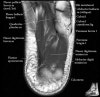

발목 관절의 MRI 단면 영상

- Sagittal section

Bones and marrow

Joint fluid

Talar dome

Subtalar joints

Achille's tendon

Sinus tarsi

Plantar fascia